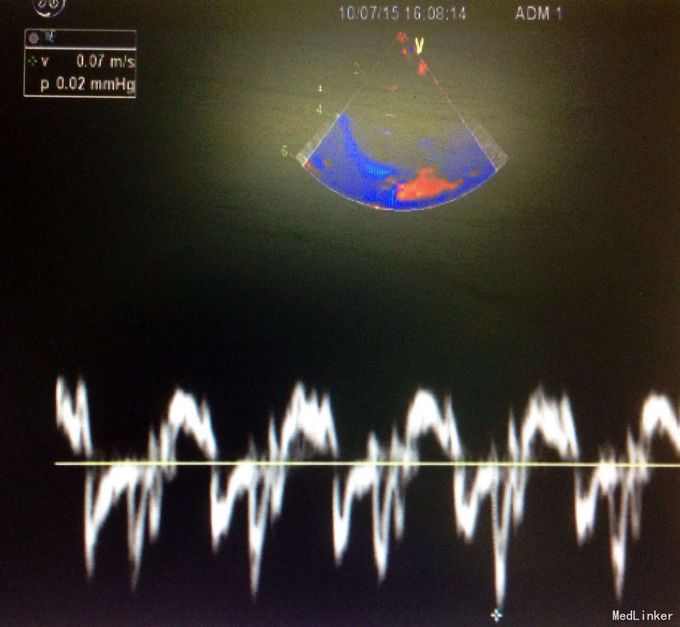

体检:生命体征正常,全身皮肤黏膜无黄染,腹隆,肝脾肋下未及,宫高29,腹围88, FHR148,头位,未触及宫缩,未行内诊,骨盆外测量22-26-18-8 辅助检查:2周前外院检测总胆汁酸25umol/L,一周前复查总胆汁酸60umol/L,今日外 院B超示晚孕,单活胎,头位,胎儿房间隔中部囊样无回声,考虑膨胀瘤可能,本院检查 结果如下图

入院诊断:孕39周待产,G2P1,ICP 诊疗经过:患者入院后给予护肝等对症支持治疗,顺娩1活女婴,分娩后子宫收缩好,新 生儿心脏彩超示动脉导管未闭,拟随访。